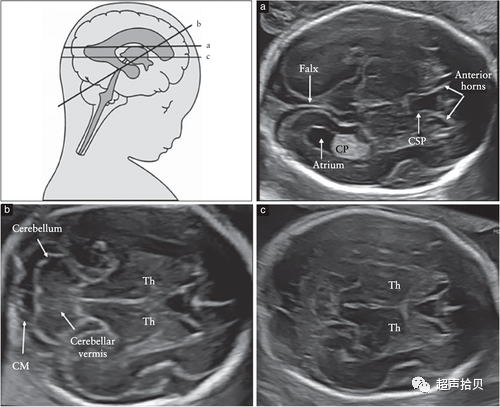

应常规评估胎儿颅骨的四个方面:大小、形态、完整性和骨密度。可在胎头部测量或评估大脑结构完整性的同时观察上述特征(图 2)

图2胎儿头部的横切面,显示标准的经脑室(a)、经小脑(b)和经丘脑(c)扫描平面。经脑室和经丘脑平面允许评估大脑半球区域的解剖完整性。经小脑平面允许评估后颅窝的小脑和大池(CM)。CP-脉络膜丛、CSP-透明隔腔、TH-丘脑。

用于胎儿大脑基本检查的标准扫描平面在更新的 ISUOG 指南20中有描述。两个横断面,通常称为经脑室平面和经丘脑平面,可以显示与大脑解剖完整性相关的大脑结构(图 2)。成像伪影掩盖了近端半球(更靠近探头的半球)。应添加第三个横断面-经小脑平面来评估后颅窝。应评估以下大脑结构: